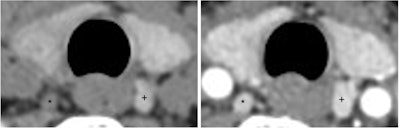

If a parathyroid adenoma is identified on preoperative imaging, a targeted approach to the involved gland may be undertaken at the time of surgery (Figure 3). When a single abnormal gland is identified and removed, intraoperative PTH monitoring is a useful adjunct to determine completeness of surgery. Varying criteria have been proposed to define an appropriate PTH reduction. A 50% reduction from a baseline pre-incision level at 10 minutes after gland removal with the final PTH in the normal range is correlated with a high likelihood of cure (normal calcium at six months postoperatively). In the absence of preoperative localization or appropriate PTH reduction after targeted adenoma removal, a four gland (bilateral) exploration should be undertaken.

Figure 3. Minimally invasive left interior parathyroidectomy. Left Inferior parathyroid adenoma (*) and left thyroid lobe (+).Figure 3. Minimally invasive left interior parathyroidectomy. Left Inferior parathyroid adenoma (*) and left thyroid lobe (+).Hypocalcemia